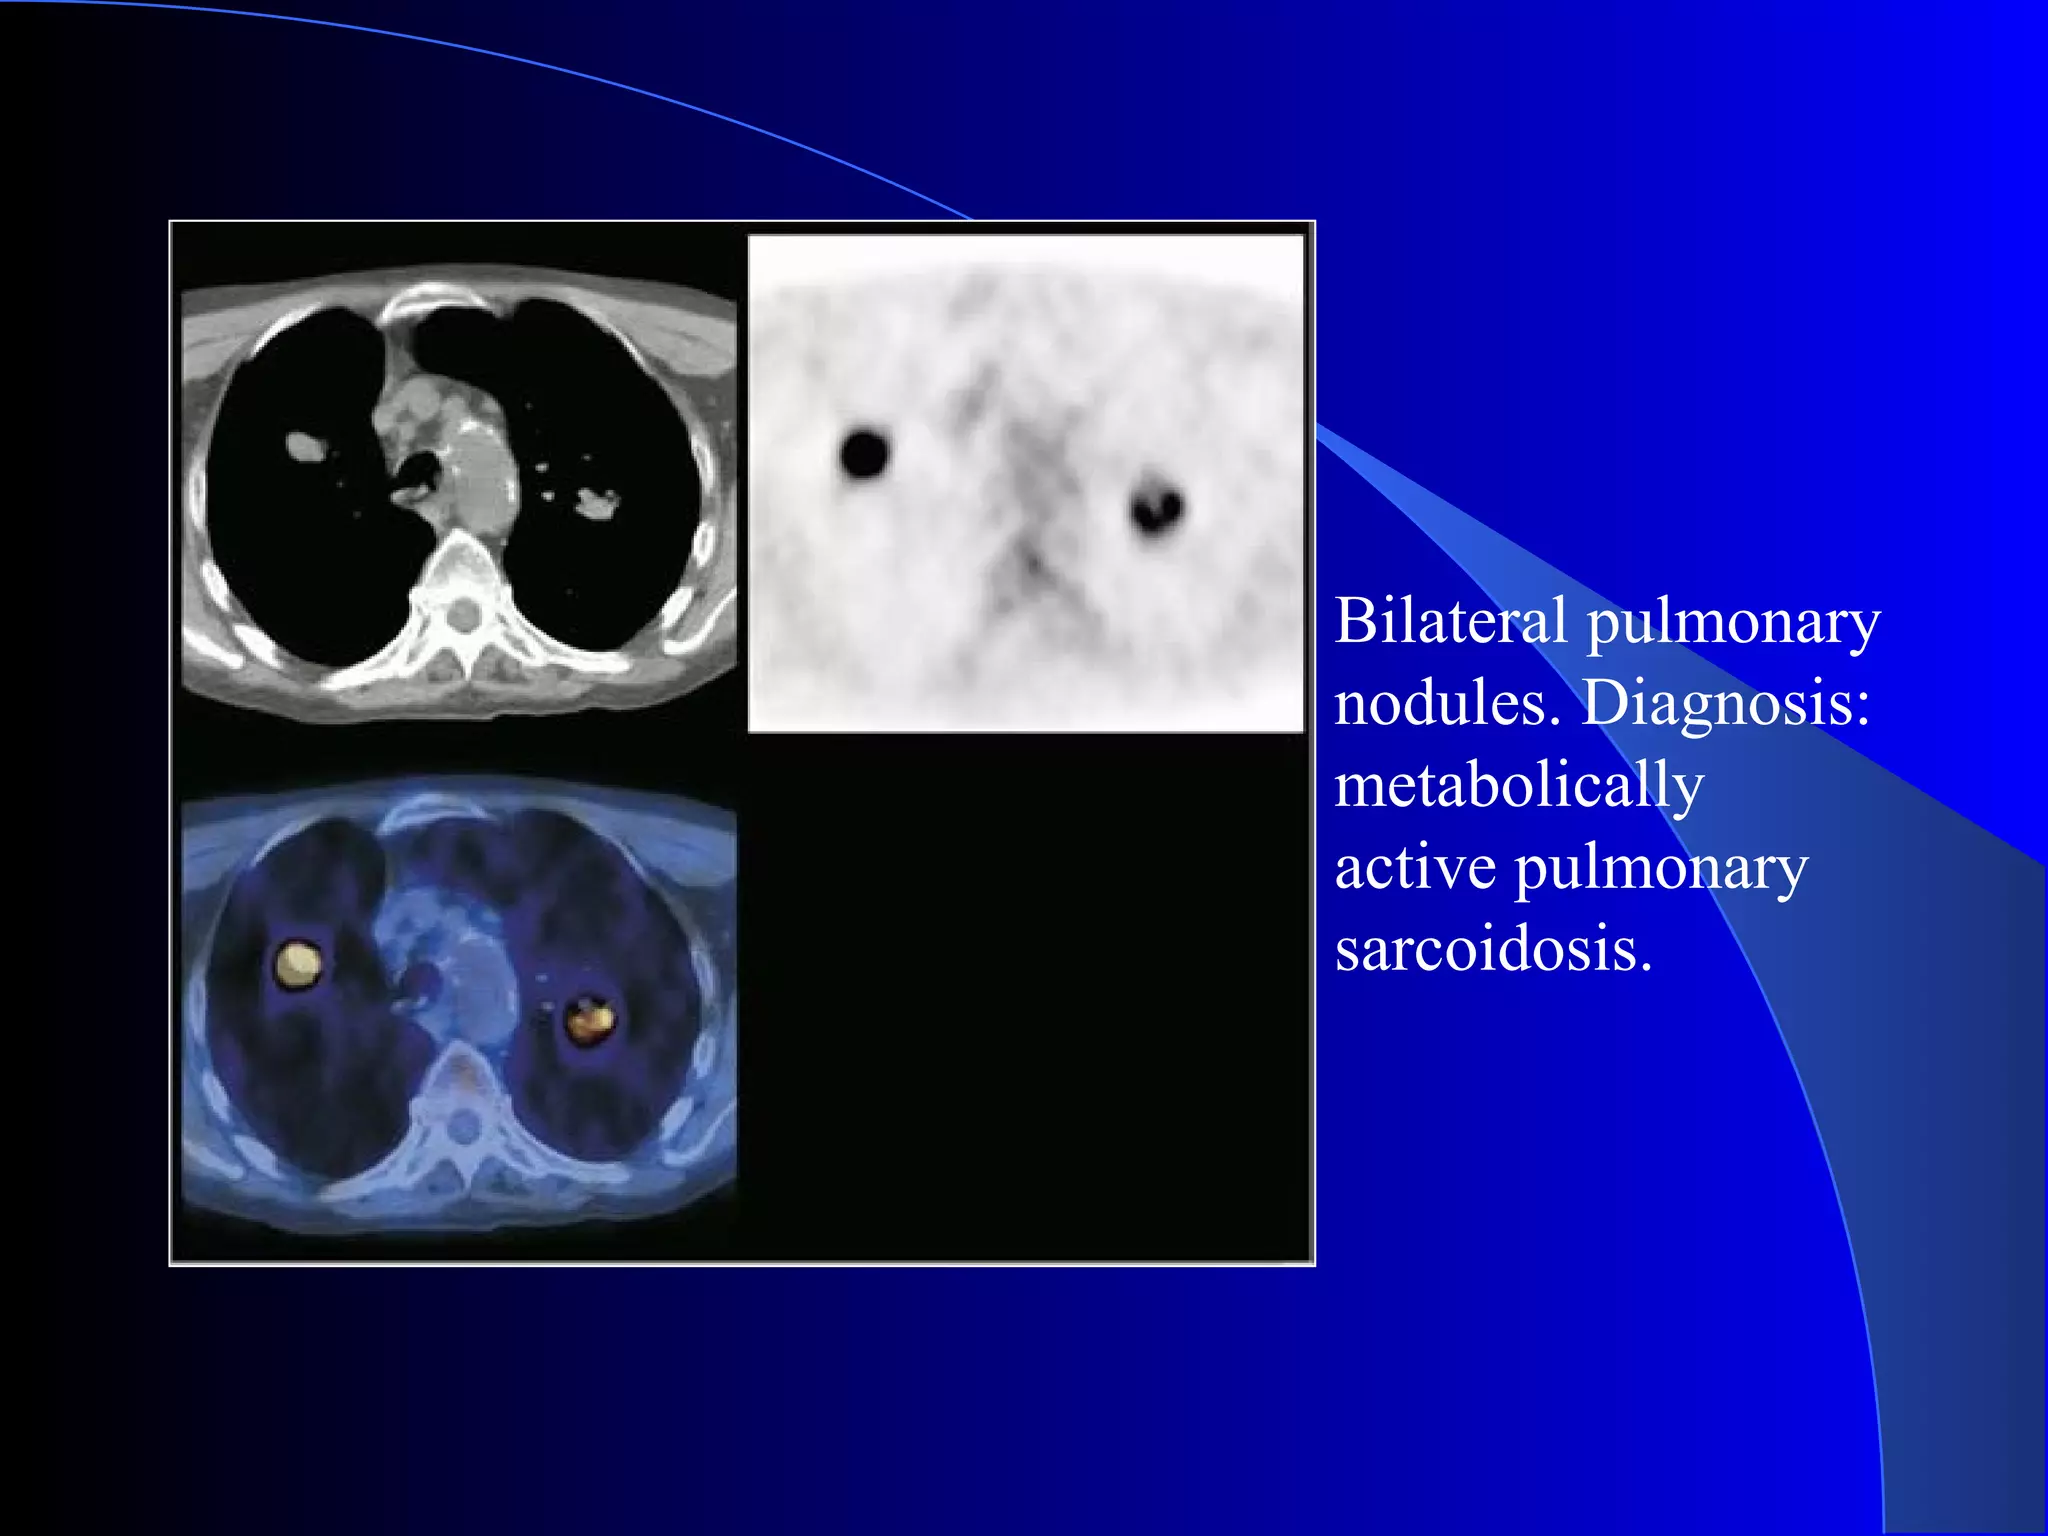

Bilateral pulmonary

nodules. Diagnosis:

metabolically

active pulmonary

sarcoidosis.

False positive SPN False negative SPN

1.Granulomas BAC

2.Sarcoidosis Scar adenoca

3.Infection carcinoids

4.Adenomas

5.Hamartomas

6.Neurofibromas